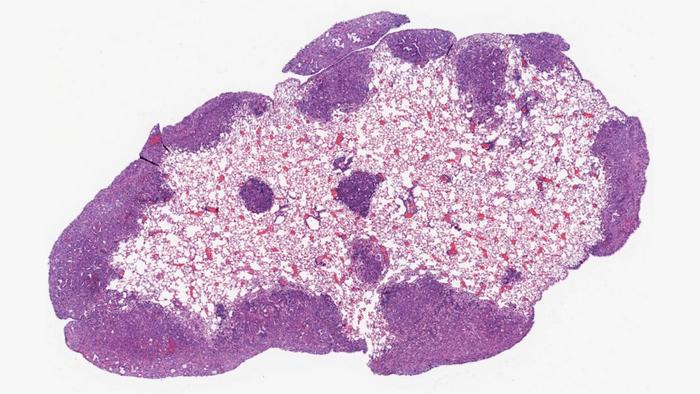

The team used organoids—mini versions of tumors—to identify the role of over-expressed EN-1 in PDAC. They found that higher levels of the aberrant protein blocked genes associated with natural cell death. When EN-1 expression was curtailed, the genes it targets were able to do their job, promoting healthy cell survival.